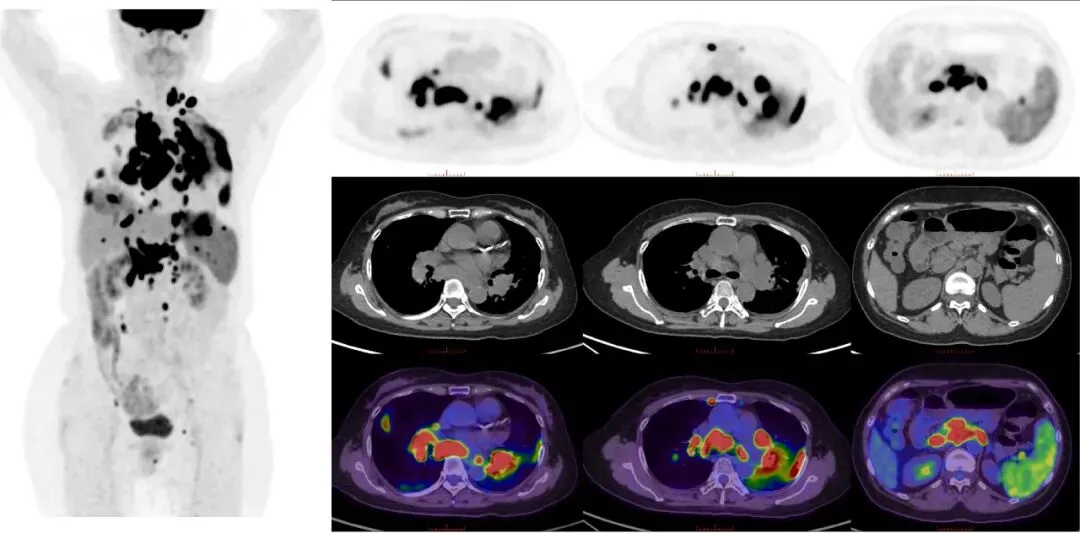

CASE 1

女,64岁,发现淋巴结肿大3月。患者3月前因“右胸背部疱疹后疼痛2月”入我院疼痛科,查CT提示双肺门及纵隔、肝门区及腹膜后多发肿大淋巴结影,淋巴瘤?同时血常规提示三系减少。我院18F-FDG PET/CT示左锁骨上窝、双肺门及纵隔、心膈角区、肝门、腹膜后、肠系膜、脾门多发淋巴结,部分肿大、融合趋势,糖代谢异常增高;双肺多发斑片影,糖代谢增高;脾脏稍增大,糖代谢轻度增高。